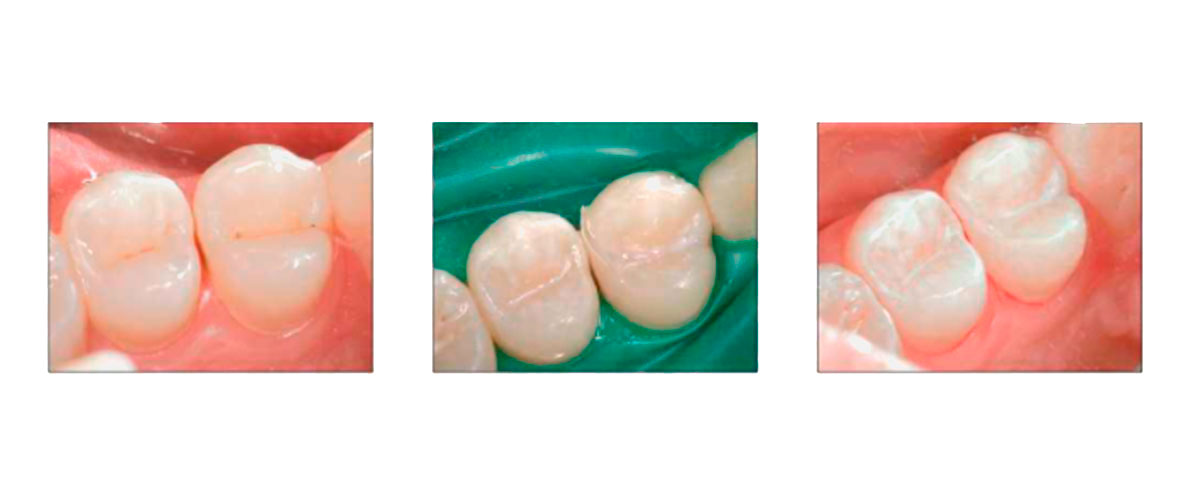

En la actualidad contamos con más y mejores recursos para poder realizar una endodoncia exitosa y de ésta forma salvar una pieza dentaria que sufrió una caries grande o una fractura (que son las causas más comunes por las cuales realizamos este tratamiento).

En OdontoCi contamos con profesionales capacitados y equipamiento acorde para que si necesitas pasar por este tratamiento las cosas salgan como lo esperás. Otro punto importante relacionado a este tema es que, así como cuando se realiza un implante el objetivo final no es el implante en si mismo, si no la resolución protética que será posible instalar en boca por medio de ese implante, cuando realizamos una endodoncia, la hacemos con el objetivo de que esa pieza dentaria o ese resto de pieza dentaria puedan quedar viables para recibir algún tipo de restauración, incrustación o prótesis que permitan devolver la función y estética perdidas. Siguiendo el horizonte de mínima invasión que nos caracteriza, no realizamos pernos metálicos, si no postes de fibra de vidrio e incluso tratamos de evitar colocarlos siempre que se pueda, así como también evitamos realizar coronas siempre y cuando sea posible devolver las estructuras perdidas de una forma más conservadora.

Algunas de las restauraciones que realizamos luego de una endodoncia son:

• ⦿ Restauración con resinas compuestas.

• ⦿ Incrustaciones cerámicas o de resinas con refuerzo cerámico (sector posterior).

• ⦿ Endocrown (coronas sin anclaje intraradicular).

• ⦿ Coronas libres de metal sobre poste de fibra de vidrio.

• ⦿ Carillas cerámicas o de resina (fracturas dentarias en el sector anterior).